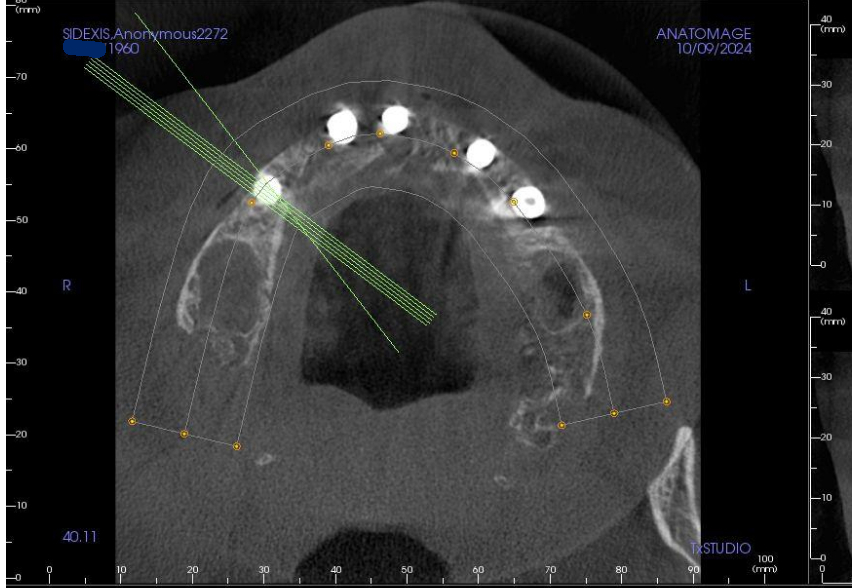

Earlier I mentioned that after trying to ignore the problem that the Michigan dentist had found two weeks earlier, Dr Shobhit Bansal grudgingly did a CT on September 12, 2024, then admitted there was a problem but tried to downplay it. Then Bansal specifically told me that everything else with the All on 4 was perfect.

The near total lack of bone at the right lower rear implant, and all the other problems with the implants, already existed when the first periodontist took a CBCT and xrays on October 9, 2024, less than one month after Bansal said everything was perfect. Clearly all those problems did not magically develop overnight.

After reviewing CBCT and additional high definition xrays of each implant, a prosthodontist with 40 years experience wrote in his report:

"... the last implant on the lower right side has practically no bone, the last implant on the lower left has about 70-80% bone loss. Both implants should be removed. One implant in the middle is not being used ... "

There is also an unused implant buried in the center of my lower jaw which has severe bone loss which all the experts said must be removed. That implant poses a significant threat to my health. The bone loss pocket surrounding that implant is a magnet for pathogenic anaerobic bacteria that can have a devastating effect on my jawbone. This condition leads to progressive bone destruction, implant failure, and significant cosmetic changes.

That unused implant has mystified the dental experts. None of the dental experts could understand why an implant would be placed and then not utilized. All three of those lower front implants were placed at the same time after Bansal mangled my lower jaw the first time. Bansal never tried to incorporate that implant to the prosthesis, it was Bansal's plan not to use that implant from the day he buried it in my jaw. Now all three lower front implants need to be removed and a great deal of bone and gum grafting will be required afterwards.